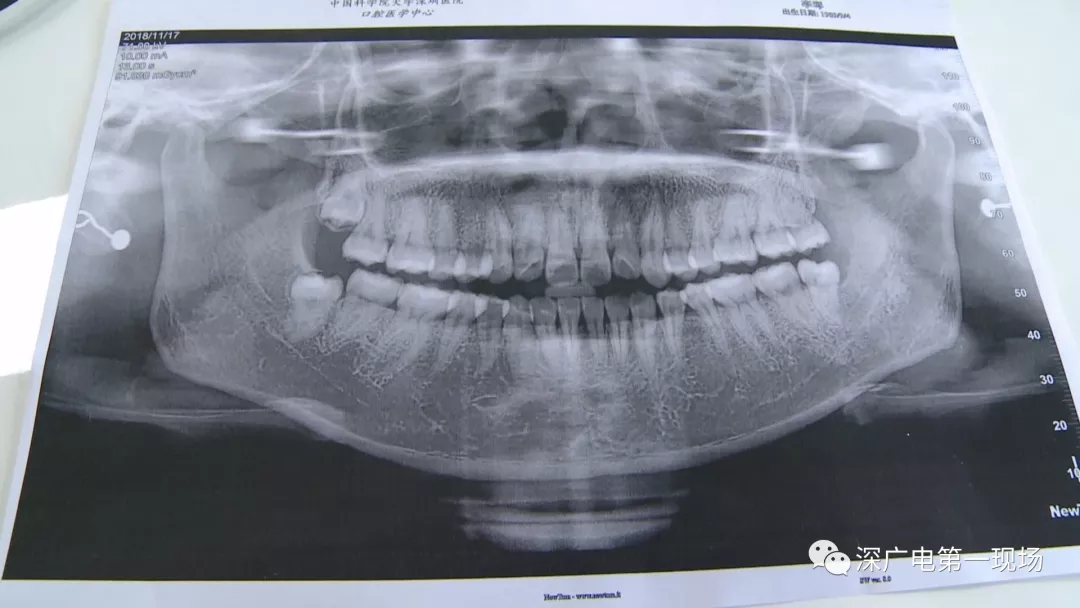

中國(guó)科學(xué)院大學(xué)深圳醫(yī)院口腔科主任賈岳介紹,對(duì)于不同患者的牙齒,它的治療方法都不一樣,所以不同牙齒,醫(yī)院收費(fèi)的標(biāo)準(zhǔn)也各不相同。牙齒的治療方案,都是根據(jù)患者牙齒具體情況來(lái)制定,然后再去收費(fèi),同時(shí)也會(huì)參考病人實(shí)際情況來(lái)做不同的治療項(xiàng)目。